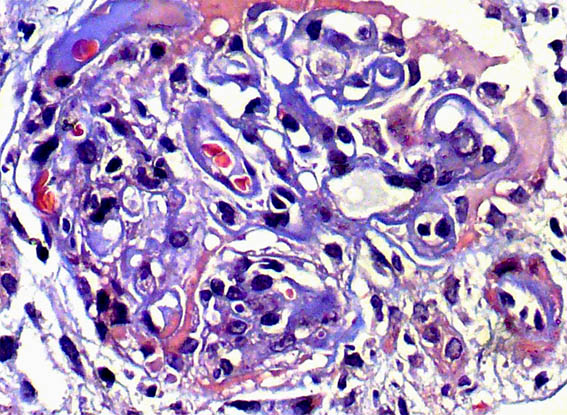

Figure 3. H&E, X400.